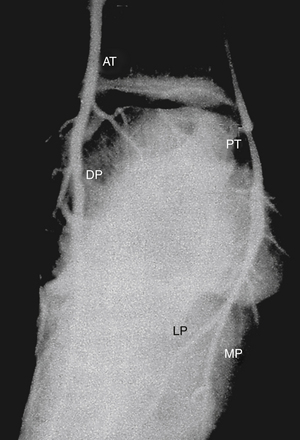

РИСУНОК 13-13. Косой вид правой стопы. Передняя большеберцовая артерия (АТ) переходит на тыльную поверхность стопы, где становится тыльной артерией стопы (DP). Задняя большеберцовая артерия (ПТ) проходит позади медиальной лодыжки и вскоре после этого раздваивается, образуя медиальную подошвенную (МП) и латеральную подошвенную (ЛП) артерии. Подошвенный свод стопы образуется путем слияния латеральной подошвенной артерии с подошвенной плюсневой ветвью (не показана) тыльной артерии стопы. Подошвенная дуга дает начало плюсневой и пальцевой ветвям.